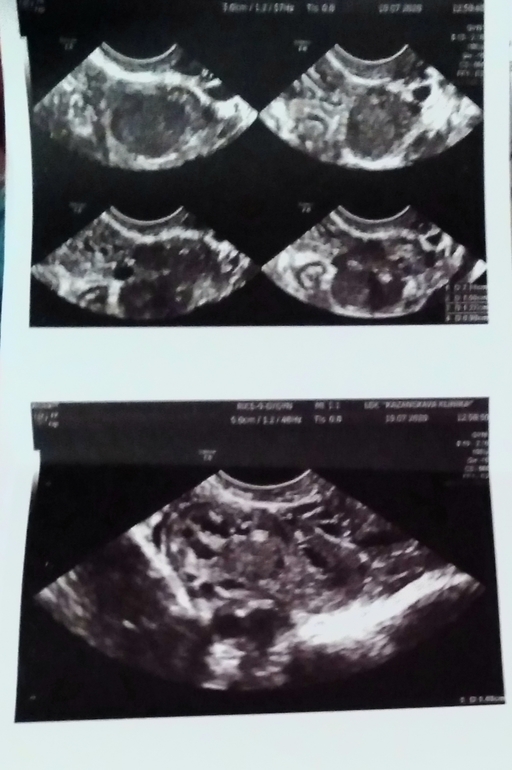

Один гинеколог думает, что кисты трехкамерные, исходя из снимков по УЗИ, их общий размер 5 см на одном яичнике на другом тоже есть кисты